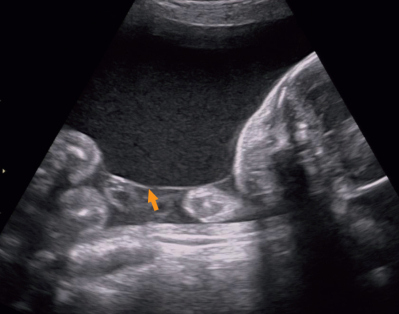

38 歳の初妊婦。妊娠 24 週に急激な腹囲の増大と体重増加を主訴に来院した。体外受精 - 胚移植〈IVF-ET〉で妊娠した。妊娠初期の超音波検査で 1 絨毛膜 2 羊膜性双胎と診断されている。超音波検査で両児間の推定体重に差を認めない。 1 児の最大羊水深度を計測した超音波像と両児間の隔壁を示す超音波像を別に示す。